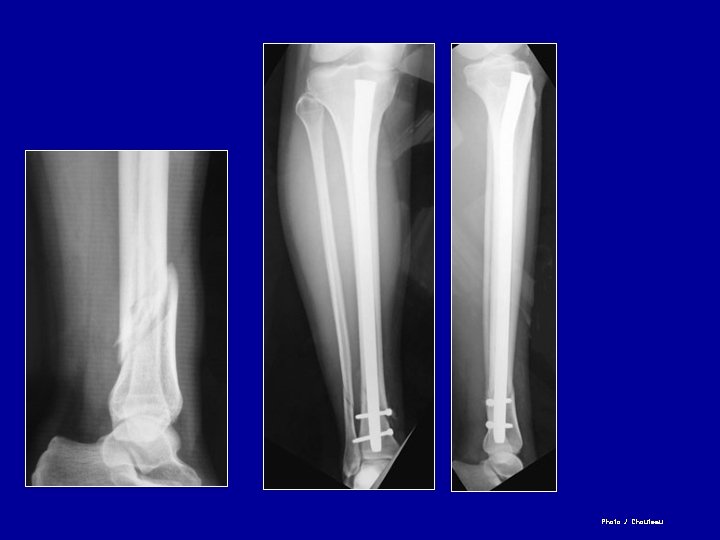

Enclouage du tibia à foyer fermé Clou simple Clou à ailettes Clou verrouillé par vis

Clou à foyer fermé verrouillé Vis enlevées à 3 mois Guérison 6 mois

Photo J. Chouteau